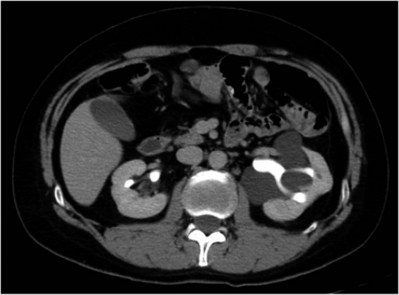

In addition to causing pain, cysts may compress the renal parenchyma or other adjacent organs, cause ureteral obstruction and obstructive uropathy, spontaneously bleed, cause hypertension, or become infected. Laparoscopic decortication or unroofing may be used to treat these cysts, which are typically simple in character (Fig. 55–22). Cysts with complex appearance, such as thickened septa, calcification, or enhancement (Bosniak class III-IV), may be explored and sampled laparoscopically to rule out renal cell carcinoma due to their increased risk of harboring malignancy (Cloix et al, 1996; Santiago et al, 1998). Options include cryoablation, enucleation, partial nephrectomy, or radical nephrectomy. If there is any question of cyst proximity to the collecting system, cystoscopy and placement of an open-ended ureteral catheter may be performed to ensure the integrity of the collecting system after cyst excision.

Figure 55–22 Axial CT scan in delayed phase after IV contrast administration, demonstrating peripelvic cysts in a patient who presented with left flank pain.